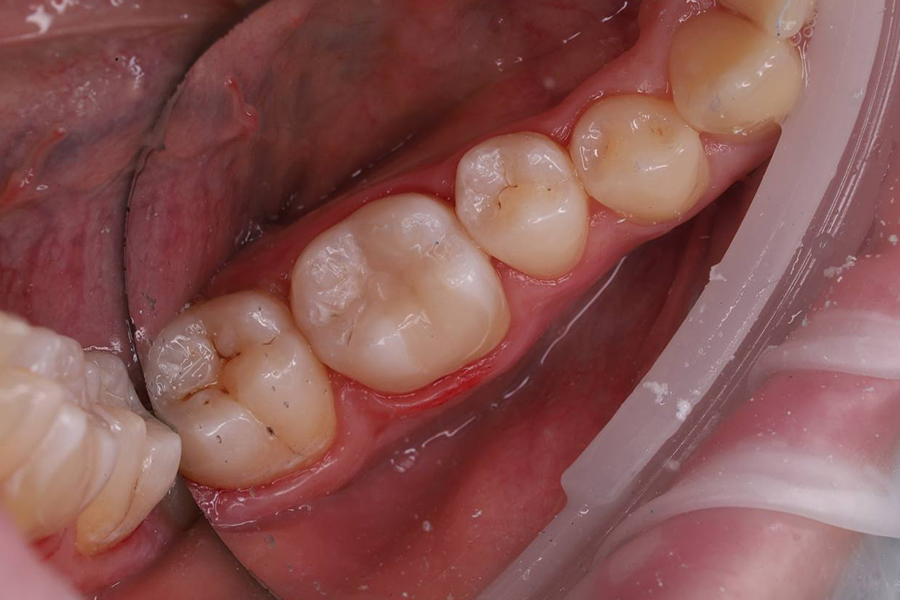

2. Коррекция пломбы по прикусу, полировка.

• Постановка анатомической светоотверждаемой пломбы.

Результат

Пациент доволен результатом, зуб после лечения не беспокоит.